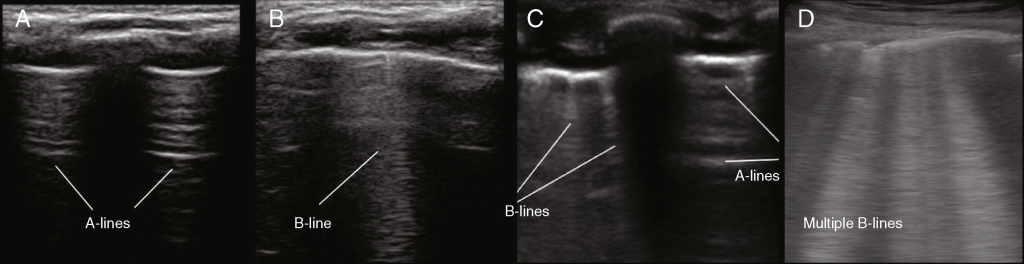

Os principais achados ultrassonográficos são:

• Ausência do “lung sliding”: indica separação entre as pleuras e ausência de ventilação regional

• Presença de “A-lines” proeminentes: reforça a reflexão aérea sem artefatos verticais

• Ausência de “B-lines”: confirma ausência de contato pleural

• Sinal do “lung point”: ponto de transição entre áreas com e sem deslizamento pleural, considerado diagnóstico de pneumotórax.

Assim, o reconhecimento desses sinais, aliado à correlação clínica, permite o diagnóstico imediato, reduzindo significativamente o tempo até a intervenção.

Fonte: jped.com.br